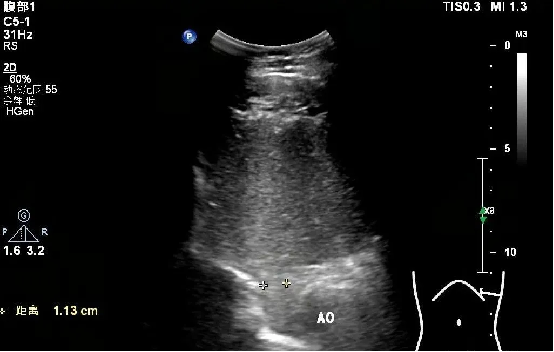

胃造影:

检查所见:贲门上方未见确切囊状扩张,观察贲门5min可见显影剂大于5次从胃反流入食管下段,最大反流束宽约12.4mm。

检查提示:胃食管反流性疾病